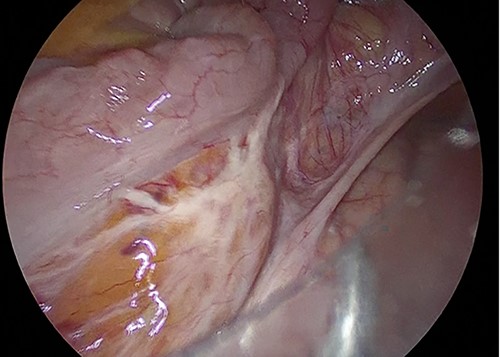

The sigmoid colon was elongated, and a scar was detected near the SD junction, which appeared to be a site of repeated torsion (Fig. 4). Dilation of the sigmoid colon revealed no inflammation on the serosal surface. The laparoscopic procedure was completed after confirming that the sigmoid colon was sufficiently elevated to the left lower abdomen. A 4-cm cross incision was made at the opposite of McBurney’s point, and the sigmoid colon was raised outside the wound (Fig. 5). The intestine was considered to be sufficiently decompressed to allow anastomosis. The intestinal tract was separated, and anastomotic reconstruction was performed using functional end-to-end anastomosis. The operation duration was 89 min, and the bleeding amount was 5 ml.

Method of Sharon operation. Sigmoid colon was raised outside the wound at the opposite of Mc Burney’s point.